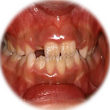

センターの治療例

30歳治療前 |

30歳治療後